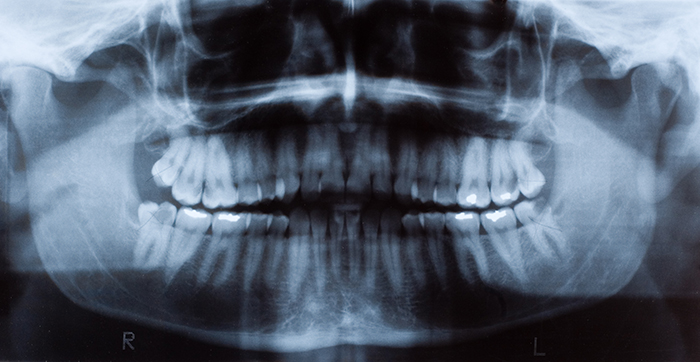

Tooth decay is the most prevalent chronic oral disease. The treatment for cavities, known medically as caries, is to remove the decayed tooth tissues and restore teeth with filling materials such as dental composites. Currently, composite restorations have a limited service life – about five to seven years -- and their replacement accounts for 60% of dental operations.

A bacterial biofilm is a slimy layer or film containing colonies of bacteria and the sticky, substance they excrete, which allows them to attach to a surface. Biofilms are more resistant than ordinary bacteria because they contain different kinds of bacteria that stick together, and the substance they excrete also forms a protective barrier around them. The biofilms on teeth are known as dental plaque. Dental plaque uses the food and drinks people consume to produce acids that break down tooth enamel leading to decay.